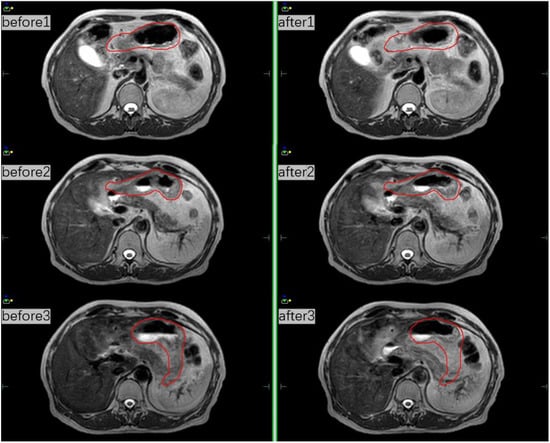

Figure 3.

MRI scans before and after treatment at three different fractions and the red line indicates the whole stomach.

The patient was then assigned an online MR-based adaptive plan and underwent radiotherapy. The intrafraction variation during radiotherapy remained stable on two MRI imaging sets before and after the treatment (Figure 3).